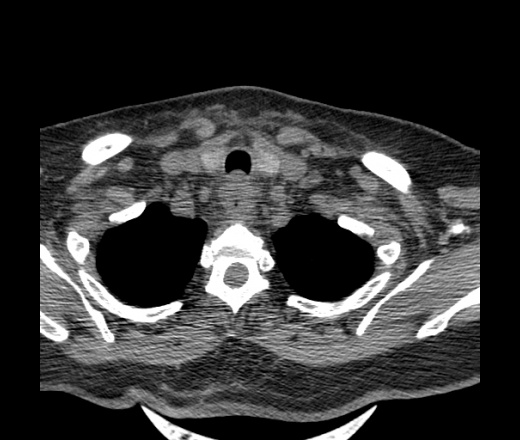

Женщина поступила в х/о спустя 4 дня после того как при употреблении карася подавилась костью.

Наличие газа в средостении на протяжении тел С2-С6 (медиастинальна эмфизема); рыбная кость на уровне тела С6.

При всем уважении, но говорить о медиастинальной эмфиземе, оценивая мягкие ткани шеи, как-то слишком резко. На мой взгляд, это ретрофарингеальное пространство.

Эвакуировали почти 100мл гноя. Но кость не смогли найти. Думаю что она даст дальнейшее ослоднение. Эндоскопически за черпалонадгортаной звязкой не смогли зайти в пищевод, все мягкие ткани отечные, просвет пищевода сдавлен. По всей видимости параэзофагеальная клетчака тоже задействована. Эмпиема, если ее можно так назвать, незнаю как правильно дошла до уровня яремной вырезки. Чем закончиться напишу. Ждем медиастинита.

Флегмона заглоточного пространства шеи, только операция, флегмоны вскрывают. Риск медиастинита.

Согласен с Вами; конечно, наличие газа в клетчатке ретрофарингеального пространства (затмение с опечаткой..). К сожалению, процесс "продвигается" к медиастиниту. Но почему никто, не отмечает наличие рыб. кости; или это для Всех очевидно?

Так вы уже отметили. Хотя ориентировал бы не скелетотопически, а на перстнечерпаловидный сустав.

Кость то мы сразу выявили, размеры где то 17*2мм, но ее так и не получается найти в этой каше